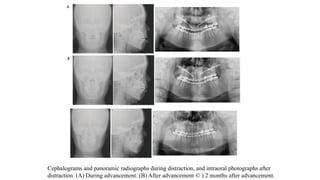

Cephalograms and panoramic radiographs during distraction, and intraoral photographs after

distraction. (A) During advancement. (B) After advancement © ) 2 months after advancement.

Orthodontic elastic traction after advancement

• After completion of the fixation, face mask therapy with the titanium miniplate anchorage

continued to stabilize the position of the maxilla without dentoalveolar compensation.

• The patient was instructed to wear the face mask for protraction regularly during the night for 2

months after completion of the maxillary advancement.

• Postsurgical orthodontic treatment was performed to achieve an acceptable overbite and overjet